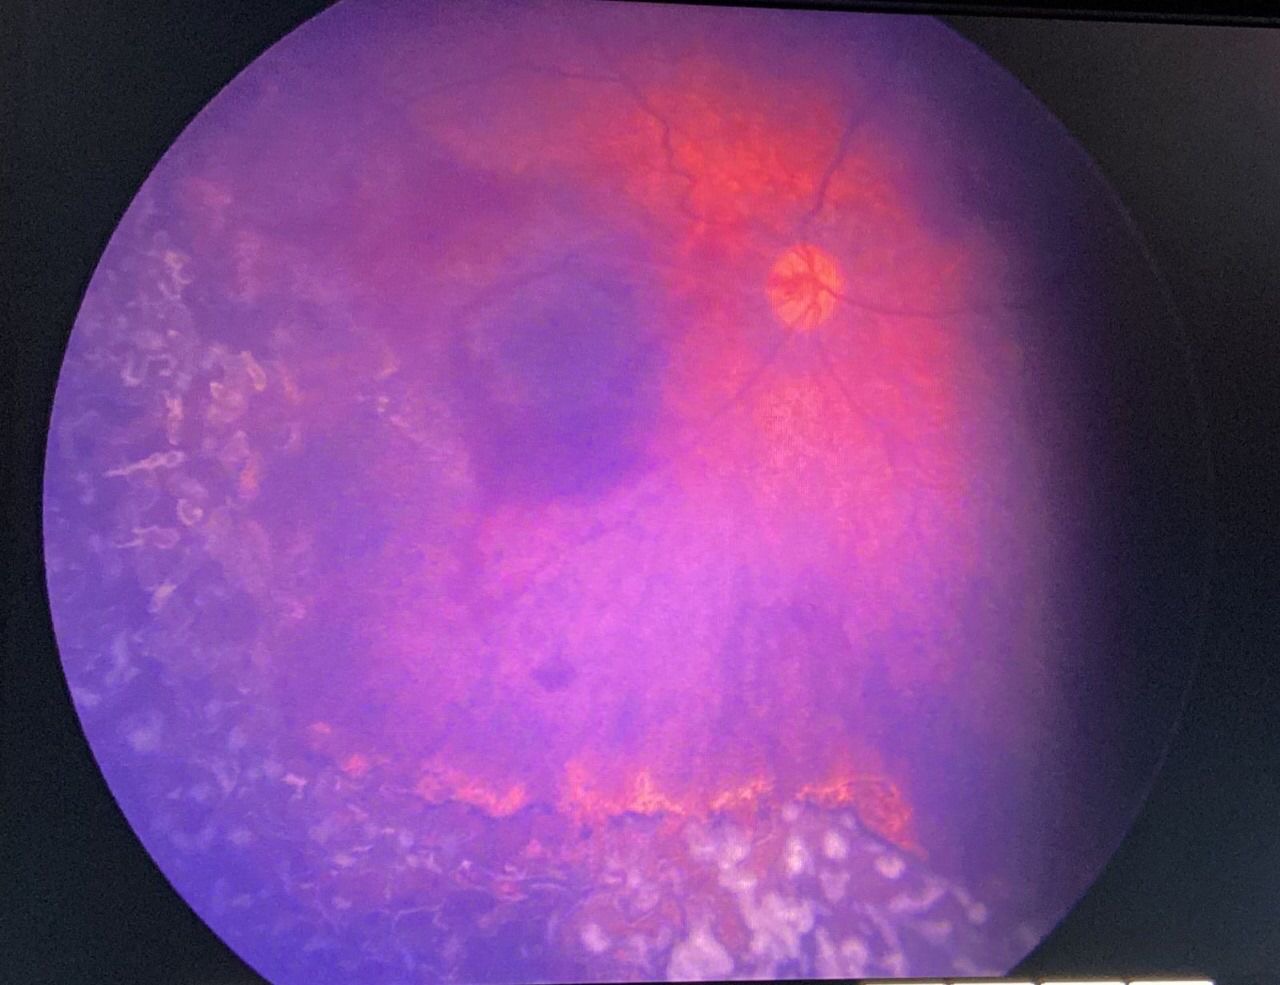

وبين التجمع الصحي أن الشبكية كانت متضررة في كلتا العينين وبالأخص العين اليمنى وأجريت عملية الليزر للعينين تحت التخدير العام بأسرع وقت ممكن وذلك بعد فحص المريضة من قبل فريق التخدير بقيادة استشاري التخدير الدكتور شادي بركات وتكللت العملية بالنجاح وخرجت الطفلة وهي بأتم الصحة والعافية دون مضاعفات تذكر أوالحاجة لأي رعاية حرجة ولله الحمد.